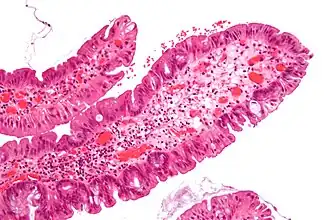

Microvesicular hyperplastic polyp. H&E stain. -